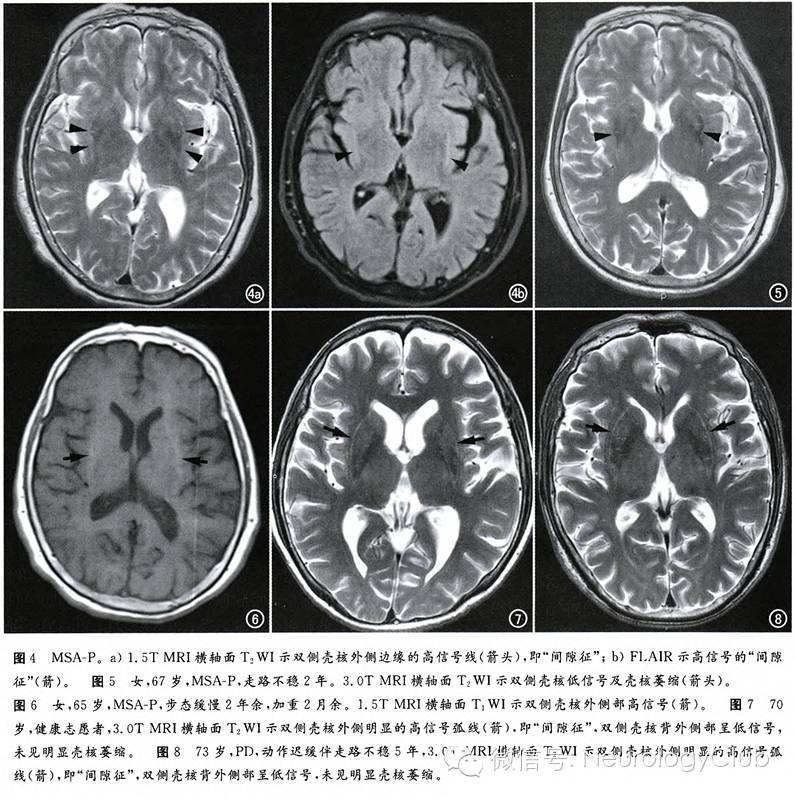

裂隙征(间隙征,Slit-like hyperintensity sign

指壳核外侧边缘T2WI高信号环Hyperintense Putaminal Rim Sign,是MSA-P在1.5T MRI上的一个特征性征象。其病理基础还不是很确定,有学者认为是由于壳核外侧神经元缺失以及胶质增生,壳核萎缩引起组织问空隙增大产生的。但在3.0T MRI检查中,壳核“间隙征”亦可见于帕金森患者以及健康人。

(65岁女性,诊断为MSA-P)

46岁健康女性。A-B:3T MRI纹状体水平T2WI和FLAIR可见双侧壳核外侧缘高信号,即裂隙征。C:1.5T MRI上未见异常。

壳核T2低信号(Putaminal hypointensity

指壳核背外侧可见等于或低于苍白球信号的异常信号,病理证实是由于铁蛋白丢失、铁沉积引起。但壳核异常信号会随着磁场强度的改变而发生改变。1.5T MRI可发现壳核T1高信号,对MSA-P也有一定的诊断价值。3.0T MRI的信噪比和分辨力提高,更容易发现由铁沉积引起的T2WI低信号,因而也容易发现正常人由于退变而引起铁沉积。尽管在1.5T MRI上,壳核“间隙征”和壳核T2低信号对于诊断MSA-P有较好的敏感性和特异性,但在3.0T MRI上,这些征象的诊断价值受到一定的限制。

壳核萎缩(Putaminal atrophy

其病理基础是神经元丢失及胶质纤维增生,对于诊断MSA-P有较高的特异性。在MRI上表现为壳核变小、厚度变薄。壳核弧度消失、变直,但是壳核萎缩判断带有一定主观性,而且在病程早期敏感性不高,限制其在临床上的应用。